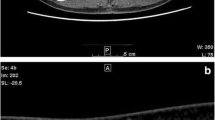

Yasaka K, Akai H, Kunimatsu A, Abe O, Kiryu S (2018) Deep learning for staging liver fibrosis on CT: a pilot study. Eur Radiol 28 (11):4578-4585. https://doi.org/10.1007/s00330-018-5499-7